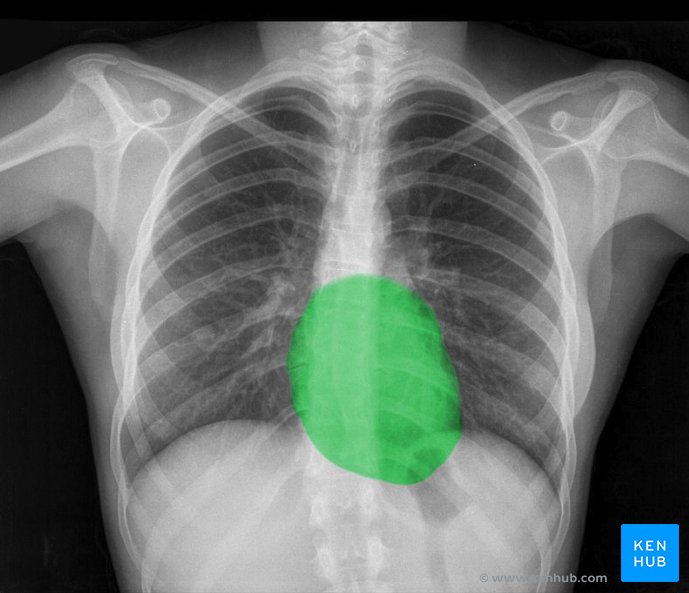

Radiografía de tórax normal: Tutorial de anatomía | Kenhub

Foto: tutorial de anatomía Kenhub